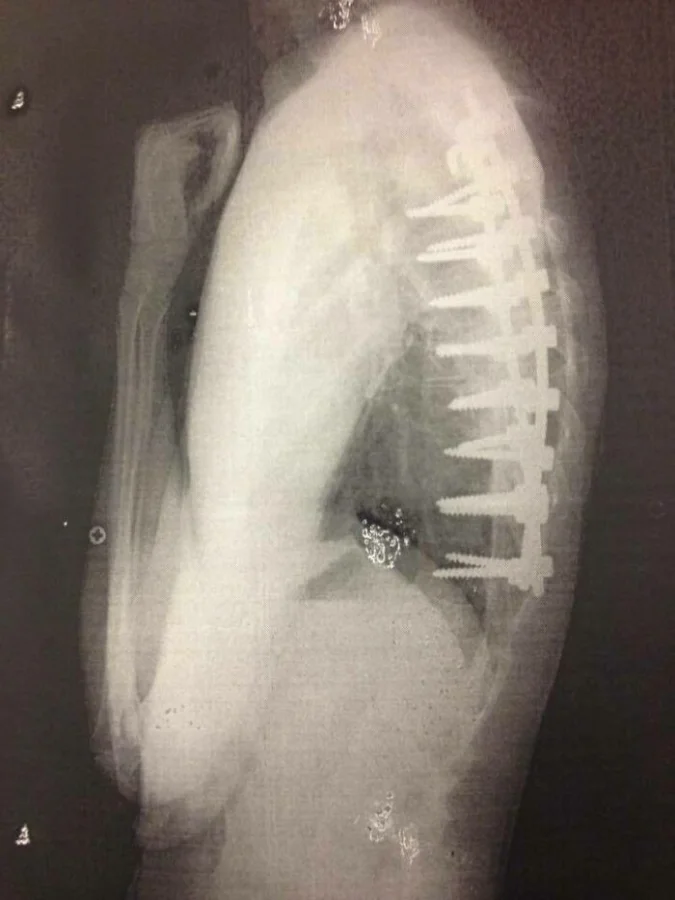

2. Это объясняет боль